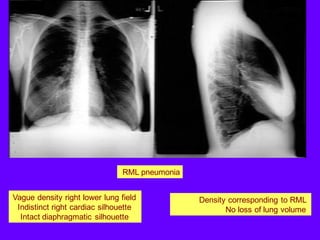

Vague density right lower lung field

Indistinct right cardiac silhouette

Intact diaphragmatic silhouette

Density corresponding to RML

No loss of lung volume

RML pneumonia